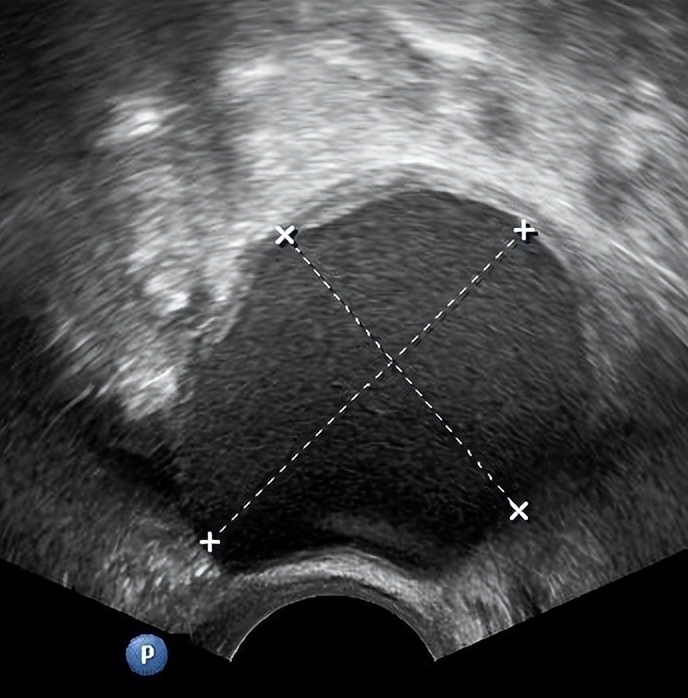

正如上文所说,由于B超下发现的毕竟只是一个影像,所以很多时候并不能判断囊肿的性质,还需要进一步观察或检查才能判断。国际卵巢肿瘤分析(International Ovarian Tumor Analysis,IOTA)组织将卵巢肿瘤的超声描述方法标准化,在以下识别卵巢肿瘤良恶性的10个简单特征中,若卵巢肿瘤含有至少一个 恶性肿瘤特征(M特征) 而没有良性肿瘤特征(B 特征),则卵巢肿瘤被分类为恶性肿瘤。

在超声检查的同时,还可以检查肿瘤标志物。当对囊肿的性质做了初步判断后,我们便可以对号入座看看如何处理。若提示有癌变风险,一般建议手术治疗。